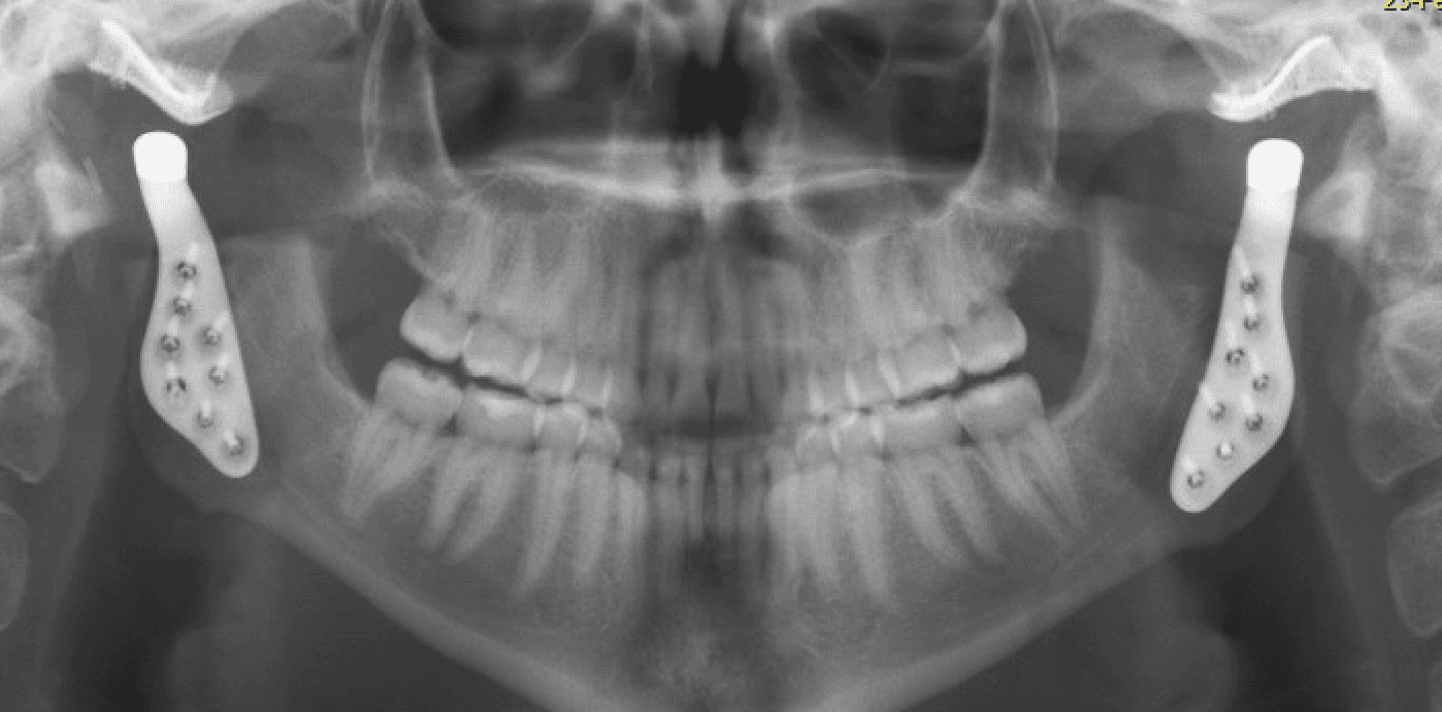

Le chirurgien maxillo-facial joue un rôle important dans le traitement des désordres temporo-mandibulaires (DTM), qui sont des affections affectant les articulations temporo-mandibulaires et les muscles qui contrôlent le mouvement de la mâchoire. Cela peut se manifester par différents symptômes allant de douleurs orofaciales, une interférence ou une limitation dans l’ouverture, un blocage en position fermée ou ouverte ou encore des cliques et craquements articulaires. Le chirurgien maxillo-facial est formé pour évaluer et diagnostiquer les DTM, en utilisant des techniques d'examen clinique, d'imagerie médicale (comme la radiographie, l'IRM ou la tomodensitométrie) et parfois des tests spécialisés pour évaluer la fonction de l'articulation temporo-mandibulaire.

Certains DTM par contre nécessiteront une approche chirurgicale en raison de leur nature ou de l’impact significatif qu’ils ont sur la fonction. En règle générale, le chirurgien tend à choisir l’approche minimalement invasive qui est la plus appropriée dans les circonstances. Cela peut impliquer une simple infiltration articulaire, une chirurgie sous caméra (arthroscopie; approche qui permet d’avoir accès et manipuler le contenu articulaire sans avoir à ouvrir) ou dans certains cas une chirurgie ouverte (arthrotomie). Les Drs Poirier et Badri détiennent notamment des expertises dans ces champs de pratiques de par leur expérience et leur surspécialisation.